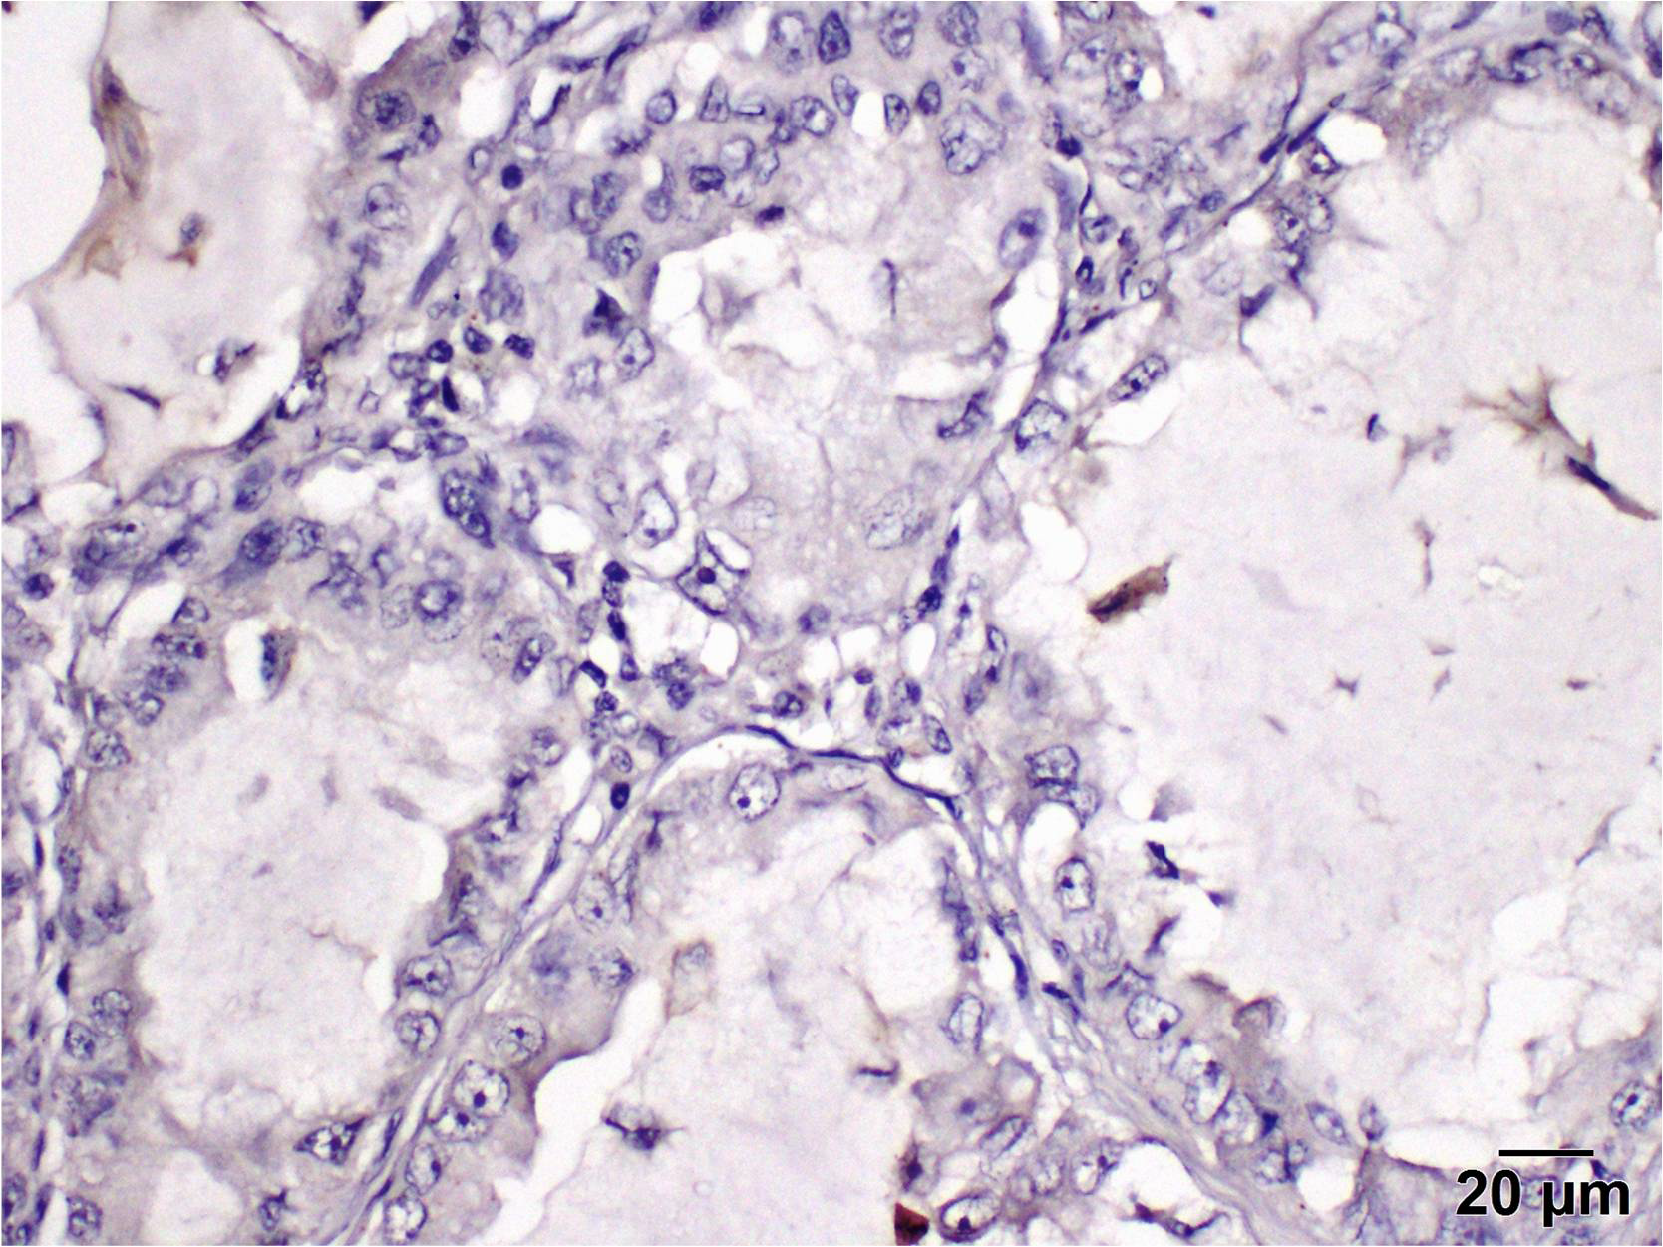

2.4. Immunohistochemistry

2.5. To Evaluate the Level of PD-L1 Expression in the Stroma, the Percentage of Positively